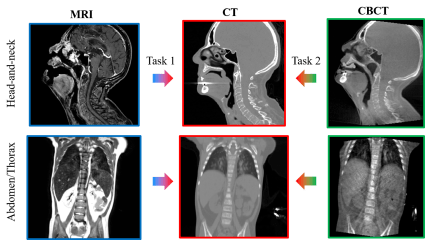

Siyuan Mei (member of LME), Prof. Dr. Ing. Yan Xia (former member of LME), and Dr. Fuxin Fan (former member of LME) achieved excellent results in the MICCAI SynthRAD2025 Challenge. The team ranked 1st in Task 2 (CBCT-to-CT synthesis) and 4th in Task 1 (MRI-to-CT synthesis). The challenge involved 673 participants, with 15 teams completing all phases. The team has been invited to present their work at the joint SASHIMI and SynthRAD workshop and will receive the award at the MICCAI 2025 conference in Daejeon, Korea. Please see more details and report at https://synthrad2025.grand-challenge.org